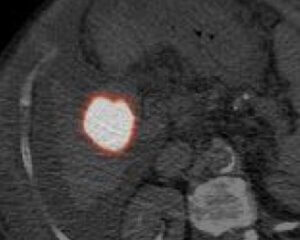

Post-y90 PET-CT

Following y-90 administration, the patient was transferred to the PET scanner for a post-infusion PET-CT, which confirmed complete tumor coverage.